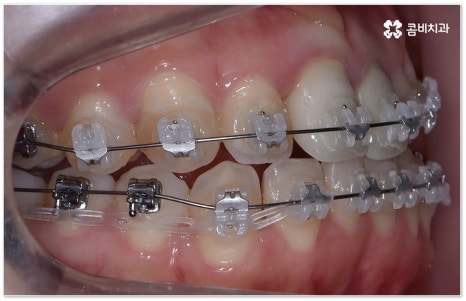

요즘 가장 많이 쓰이는 치아교정장치 인 클리피씨는 치아 색상의 세라믹 브라켓을 이용하기 때문에 심미성도 뛰어나고 자가결찰방식을 이용하여 보다 적은 힘으로 지속적이고 부드러운 치아 이동을 할 수 있도록 고안된 장치이므로 통증을 줄여줄 뿐 아니라 보통 2년 남짓 걸렸던 전체 교정 기간 역시 6개월 정도 감소시켜 줄 수 있습니다. 환자분들의 상황에 따라 내원 횟수 역시 줄일 수 있기 때문에 업무가 많이 바쁜 직장인분들의 경우에도 이용할 수 있다는 장점을 가지고 있어요.

부정교합을 개선할 때 교합이 어긋난 정도가 심하고 구조적인 원인이 커서 부분 교정이 아닌 전체 교정이 필요한 케이스인 경우라고 해도 말씀드렸던 클리피씨 교정 장치 또는 보다 심미성을 강조한 치아교정장치 들의 도움을 통해 다른 사람과 얘기를 하거나 음식을 먹을 때 브라켓이 두드러지게 드러나는 부담을 줄일 수 있으니 설측교정, 콤비교정, 투명교정, 인비절라인 등에 대해서 한 번 알아보시고 각자에게 맞는 방법으로 교정 치료를 시작해 보시길 권유드리고 있어요.